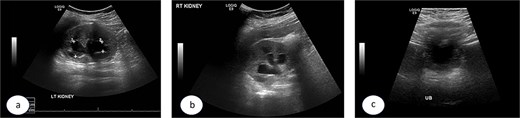

Urgent cystoscopy was performed, and bilateral double-J stents were placed. Both orifices were observed, accompanied by substantial inflammatory masses surrounding them, disproportionate to the initially injected mounds; yet, they did not obstruct the smooth passage of the stents. The patient recovered satisfactorily and was discharged with normal diuresis. One month later, the right double-J stent was extracted, demonstrating a substantial reduction of the inflammatory masses at the uretero-vesical junction. Two months post injection the left stent was removed and, at that point, no inflammatory masses were present. The mucosa appeared normal, exhibiting significant bulges at the Deflux injection sites. Subsequent ultrasound examinations revealed the absence of hydronephrosis bilaterally (Fig. 3a–c), accompanied by normal levels of creatinine and urea. The prophylactic antibiotics were discontinued and the patient was monitored for 5 years, remaining asymptomatic with no more urinary tract infections.

Ultrasound images taken 1 month after the removal of both double J stents, showing no hydronephrosis in either kidney—the left (a) and right (b)—and urinary bladder with Deflux in place (c).